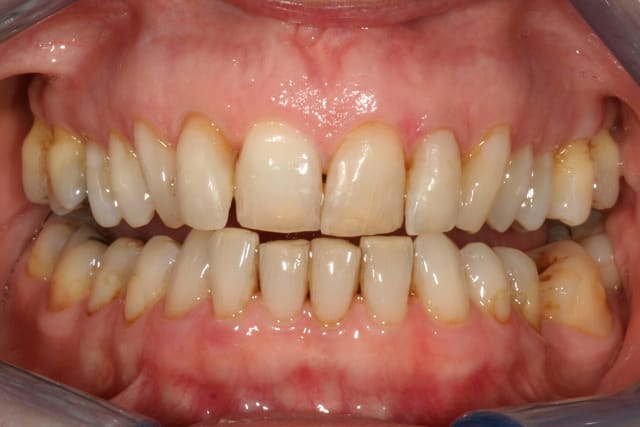

cette patiente que je suis en controle depuis 2 ans, se décide à faire quelque chose pour son sourire.

grosso modo depuis 2 ans, pas de soucis particuliers, pas de caries, faut faire un peu gaffe à la paro mais elle est plutôt motivée et ça se passe bien.

elle a plein de vieux compos d'une mauvaise couleur, au joints colorés, des dents de couleur pas vraiment toutes pareilles ; et un sourire très gingival.

pour l'occlusion, voilà les photos, il y a effectivement une classe II, plus marquée à droite qu'à gauche

elle a certes un sourire très gingival lié à la classe II, mais est-ce si grave que ça ?